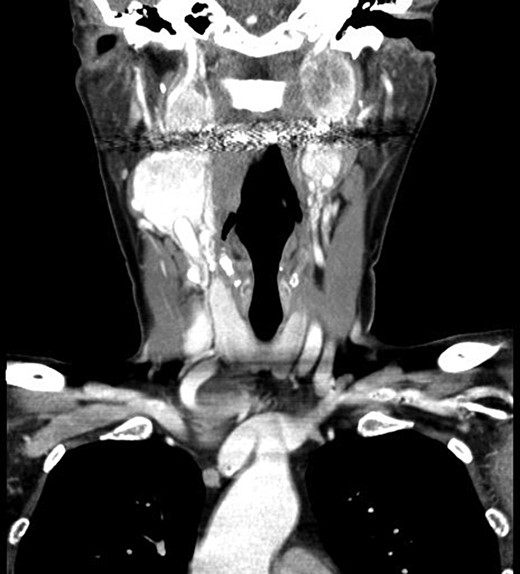

Radiation therapy was selected in the setting of local extension of the tumors and proximity to critical neurovascular structures. The patient underwent stereotactic radiation treatment of 30 Gy over 5 days, with a positive response on imaging (Fig. 2) and a reduced frequency of syncopal events.

(A and B) Magnetic resonance images, coronal planes, highlight three of the four previously noted cervical PGLs decreasing in size, with the right inferior PGL remaining unchanged.